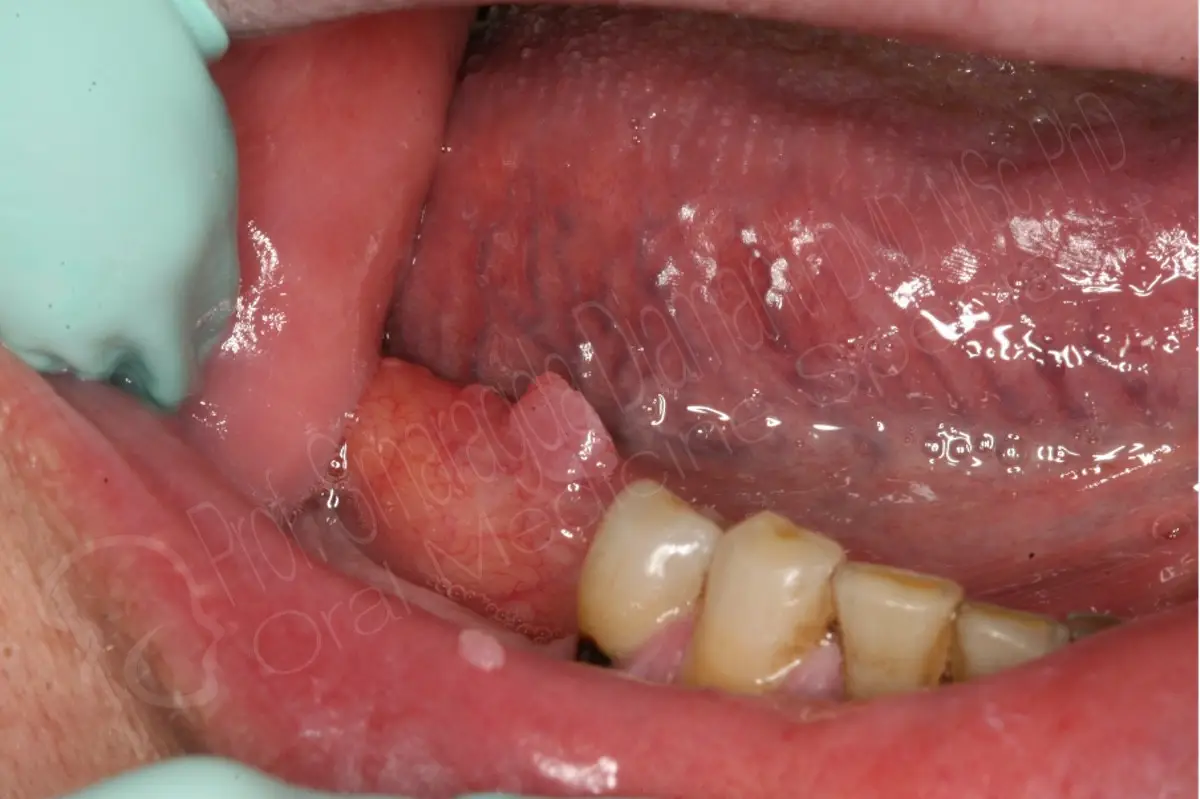

Η κλινική τους εικόνα είναι  με τη μορφή εξωφυτικού ογκιδίου το οποίο μπορεί να είναι έμμισχο ή σε ευρεία βάση, μικρών διαστάσεων, λευκού ή ροζ χρώματος με επιφάνεια ανθοκραμβοειδή, θηλωματώδη ή αποπεπλατυσμένη.

Μπορεί να εμφανισθούν σε οποιοδήποτε σημείο του στοματικού βλεννογόνου με συνηθέστερες θέσεις εντόπισης την υπερώα, τη γλώσσα και τα χείλη. Μπορεί να είναι πολλαπλά συνενωμένα ή μονήρη.